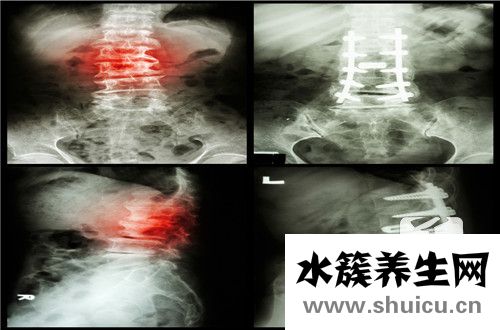

頸椎有許多功能可以控制我們整個上半身。我們所有的彎腰、起身和坐姿動作都是由脊柱和頸椎維持的。當脊柱嚴重時,會使患者感到背痛,甚至變形和突出。找到治療這種情況的方法至關重要。...